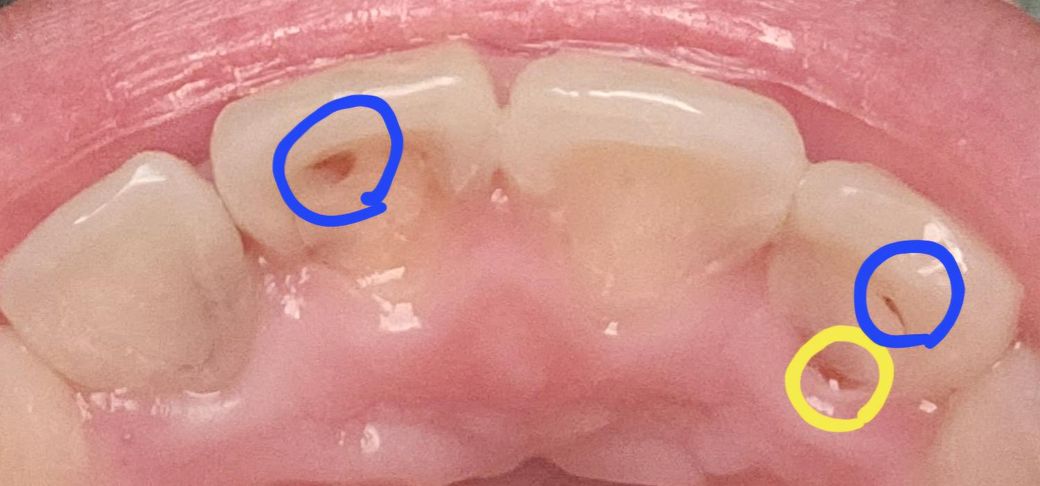

앞니 뒷면에 구멍이 생겼는데 시려요ㅜㅜ

유지장치에 문제가 있어서 철사랑 접착제를 제거했는데

접착제가 있던 자리에 저렇게 구멍이 있어요

현재 철사랑 접착제를 제거해서 구멍이 그대로 노출된 상태인데요

그리고 사진에 노란색 원으로 표시한 잇몸이랑 맞닿는 부분

저기도 빈 것처럼 보이는데

저 치아는 아예 안시린데 저 부분도 충치가 진행중인 걸까요?

• 1번 째 사진